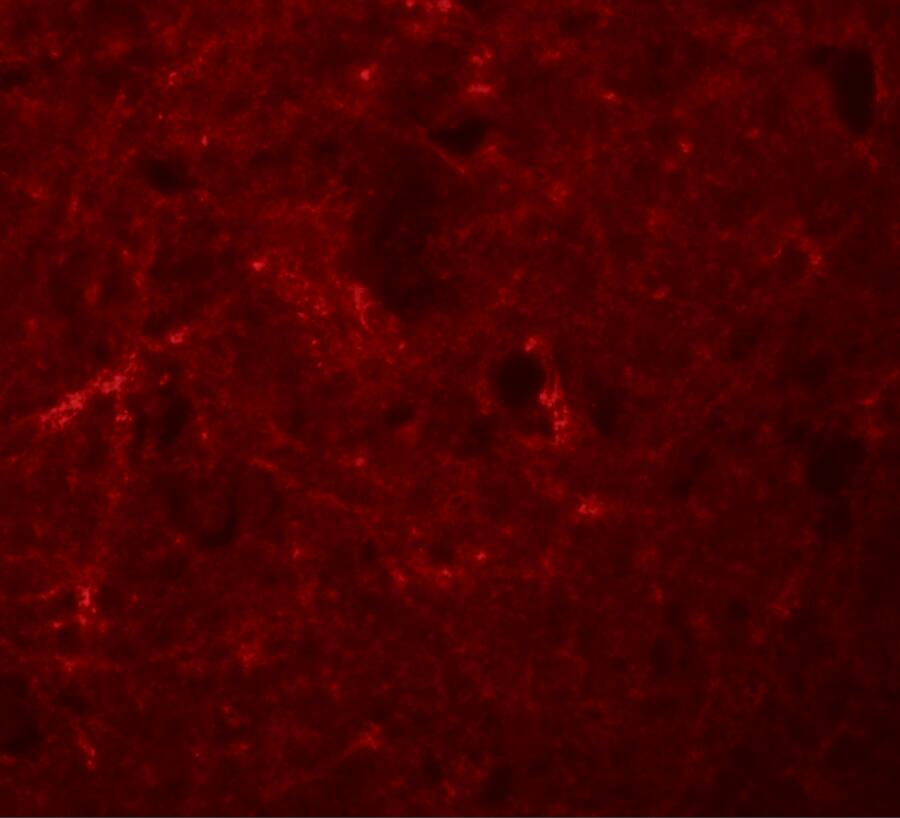

Immunocytochemistry/ Immunofluorescence: NLRP7 Antibody - BSA Free [NBP1-76290] -

Immunocytochemistry/ Immunofluorescence: NLRP7 Antibody - BSA Free [NBP1-76290] - Immunofluorescence of NLRP7 in human brain tissue with NLRP7 antibody at 20 u/mL.